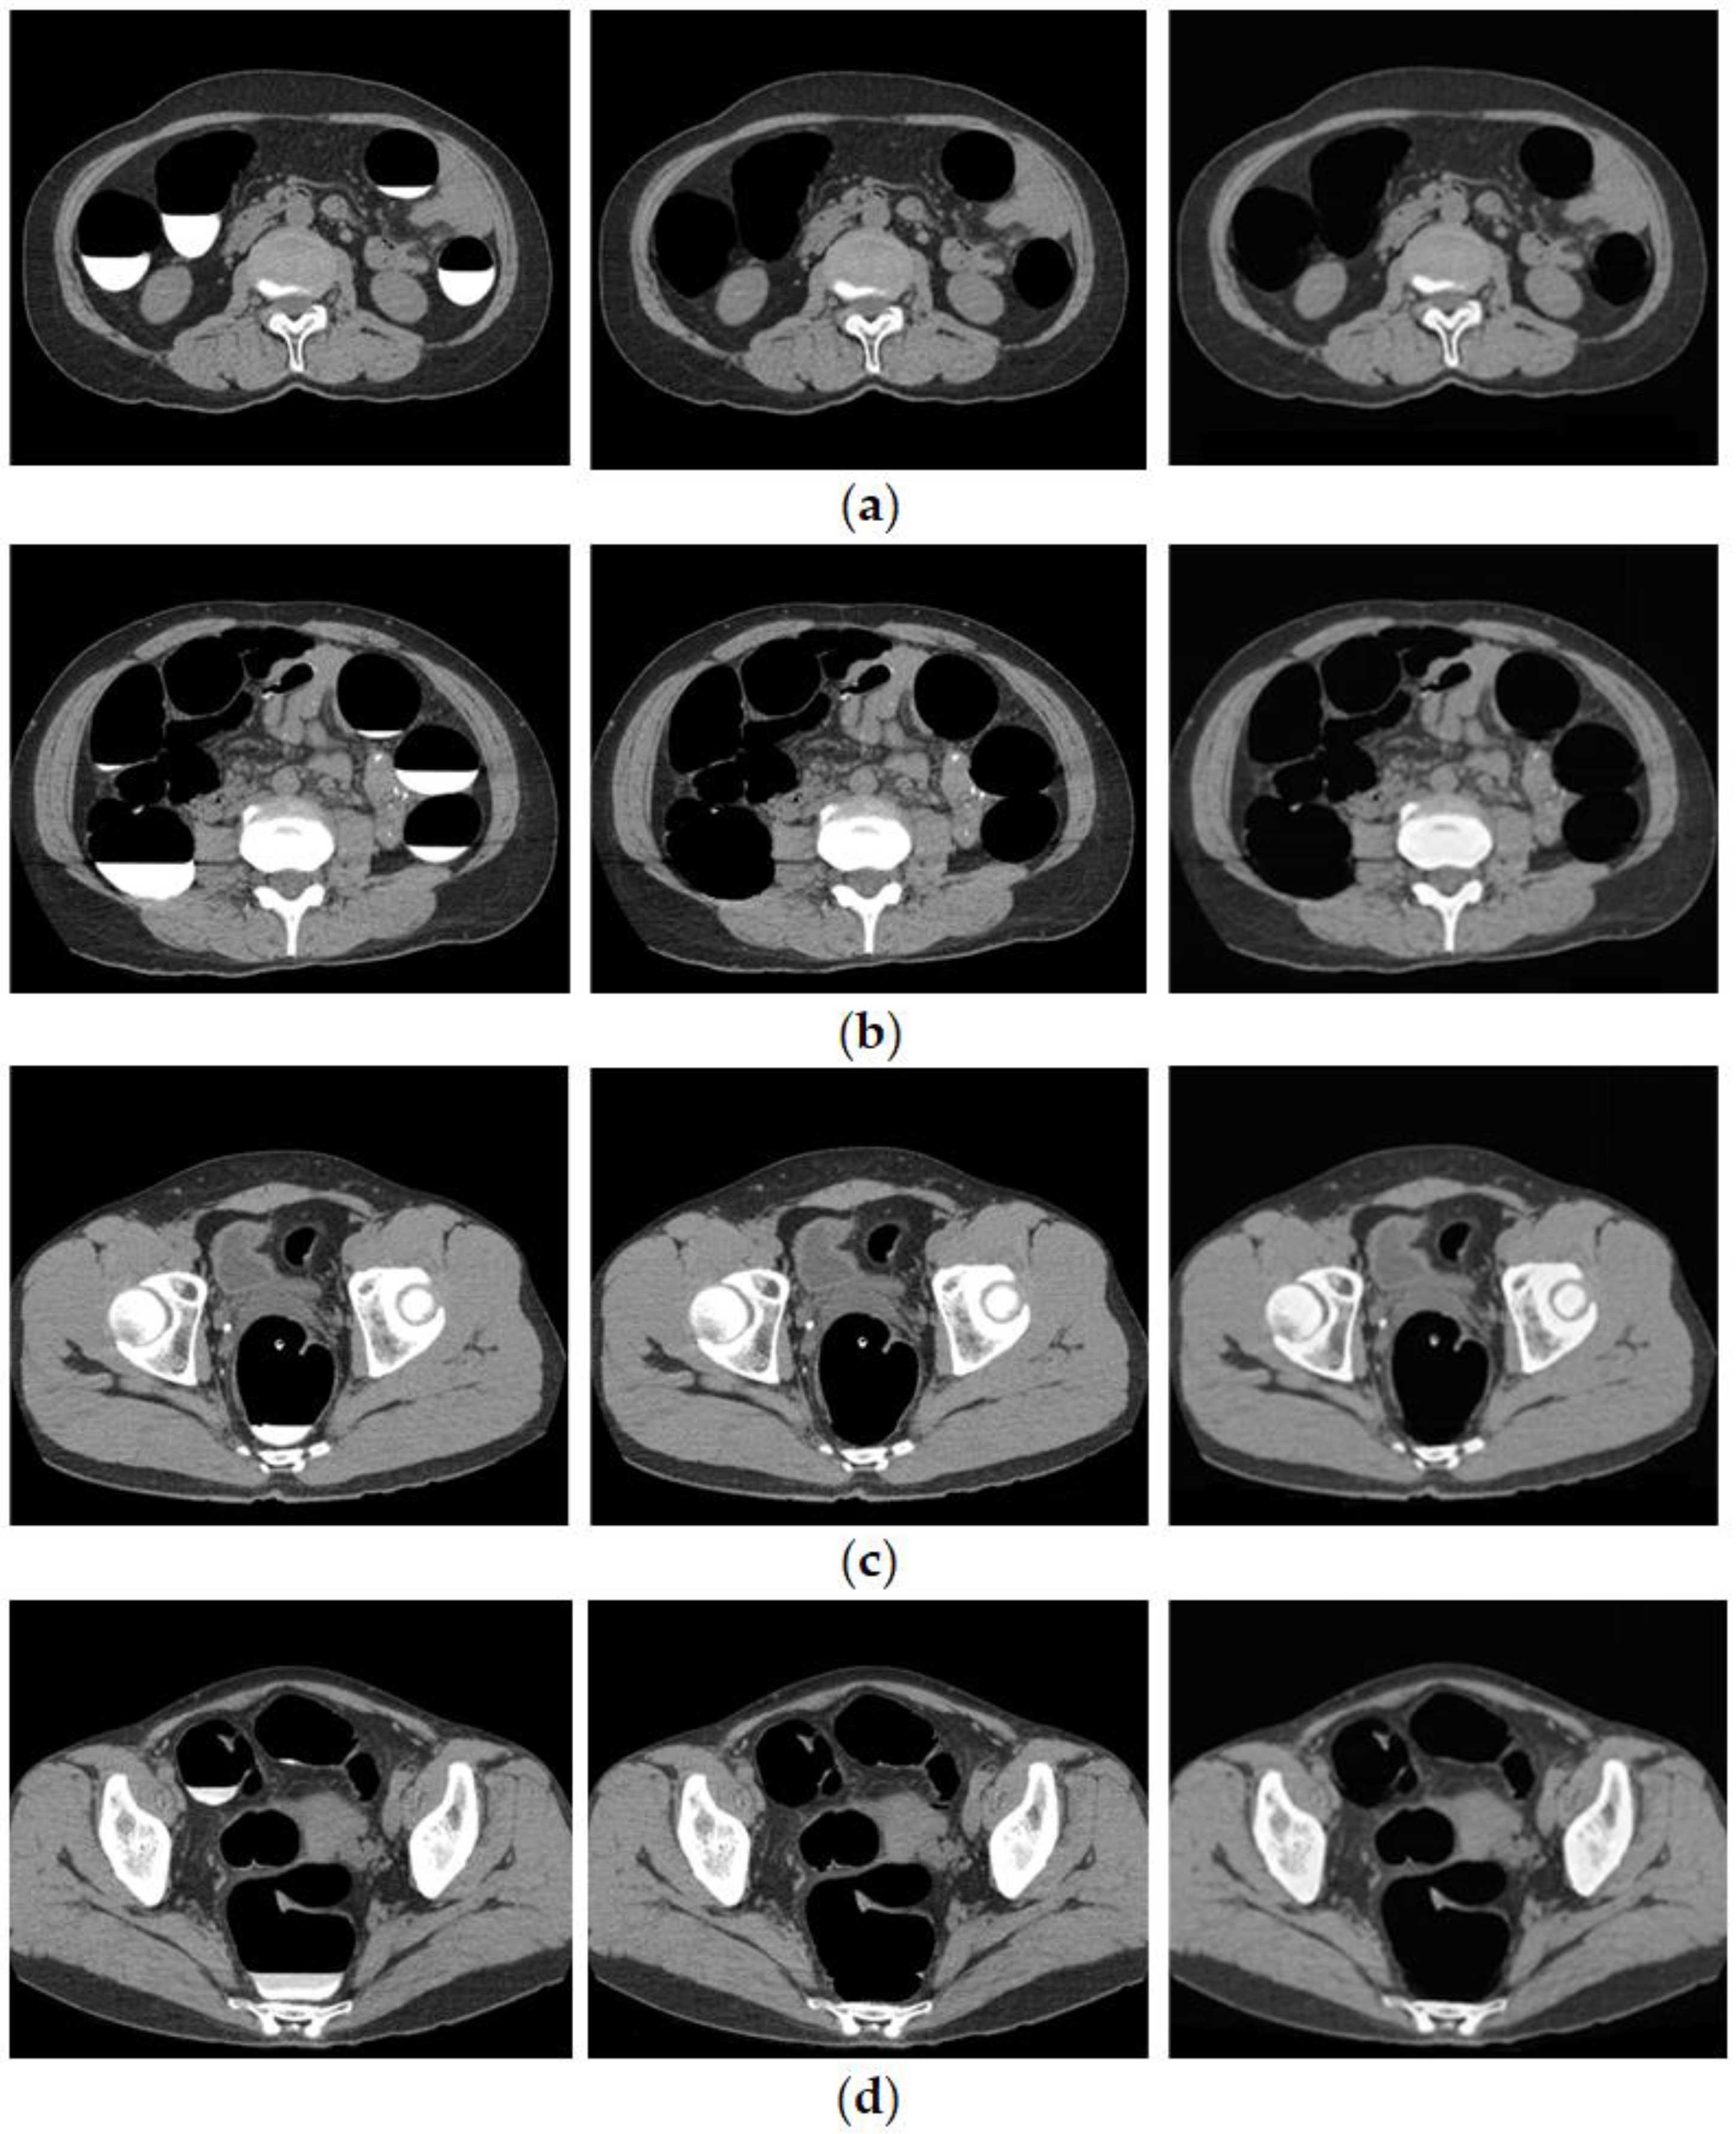

The cleansed images generated using the proposed method are shown in Figure 7. Although barium was removed up to the intestinal wall using the proposed method, no cases of excessive removal from the intestinal tract were observed.

Figure 7.

Generated image using the proposed method. (Left: original image, Middle: MC image, and Right: cleansed image using the proposed method.) (a) Ascending colon; (b) descending colon; (c) rectal colon; and (d) bad fecal tagging.

Figure 8 shows the results of bilayer separation caused by the poor pretreatment of CTC. Barium was removed even when the barium and intestinal fluid were in double layers, and the concentration of barium was not uniform. In the conventional method, a large amount of barium remained, whereas, in the proposed method, barium was removed, even at the edge of the intestinal wall.

Figure 8.

CTC image of double layer separation. (a) Original image; (b) conventional method; (c) MC image; and (d) proposed method.